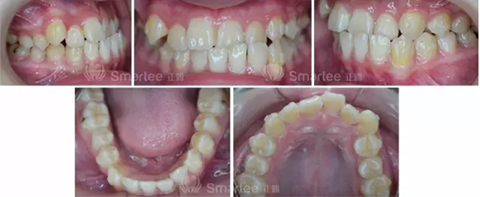

性別:女

年齡:11歲

主訴:面部左右不對稱,左側(cè)前牙反牙合。

(口內(nèi)照片)

1)安氏Ⅲ類錯(cuò)牙合

2)左側(cè)前牙反牙合

3)前牙區(qū)擁擠,個(gè)別牙扭轉(zhuǎn)

4)上頜中線右偏